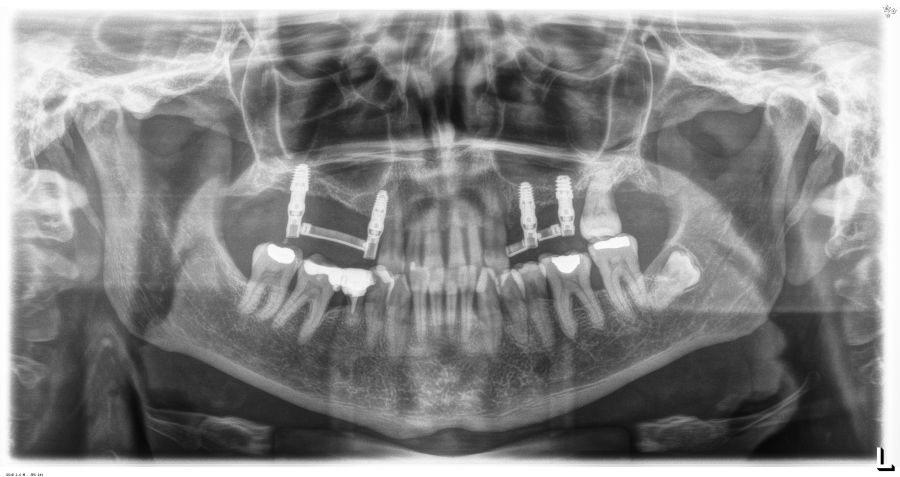

Presentamos el caso de una paciente femenina de 56 años de edad que acude a la consulta demandando un tratamiento con implantes dentales para reponer los dientes ausentes en ambos sectores posteriores maxilares. En ambos cuadrantes superiores, los molares se perdieron hace varios años. La paciente no se ha realizado la reposición de los mismos hasta ahora, ya que en otros centros consultados la propuesta terapéutica fue la de realizar injertos y regeneración ósea para poder ganar volumen óseo suficiente antes de colocar los implantes. La paciente busca otras alternativas menos invasivas y por ello acude a la visita. En las imágenes intraorales se observa la falta de los molares en los sectores posteriores maxilares con excepción del 27, que actualmente tiene un compromiso periodontal importante (Figuras 1-4). El resto de dientes también se encuentran afectados por una enfermedad periodontal avanzada con pérdida ósea horizontal (Figura 5).

Como primer paso, se realiza un escaneado intraoral de la paciente, para poder generar un encerado virtual con las piezas que queremos rehabilitar con implantes (Figuras 6-8). Esto nos permite planificar con claridad el caso y desde el modelo tridimensional, generar los provisionales y las guías quirúrgicas basadas en la posición protésica, que desde el flujo digital pueden imprimirse (Figuras 9-14). Desde el encerado podemos además generar otras guías, en este caso radiológicas, con las que realizar el Cone-Beam Computed Tomography (CBCT) de planificación. Con esta información tenemos en el mismo estudio radiológico la fusión de nuestra planificación quirúrgica y la posición real de la prótesis adaptada a la oclusión, muy útil para generar una planificación que contempla todos los parámetros. En este caso, se planifican implantes cortos de 6,5 mm en el primer cuadrante, de morfología Core-Xâ, para lograr una correcta estabilidad primaria en un tipo óseo IV como vemos en el corte seccional (Figuras 15 y 16). En el segundo cuadrante, con similares características, planificamos implantes de 6,5 y 5,5 mm de longitud (Figuras 17 y 18).

Transcurridos 6 meses desde la carga inicial progresiva, se puede elaborar la prótesis definitiva, trasladando los parámetros de la prótesis provisional (Figura 27). La paciente continúa en seguimiento durante un año, realizándose radiografías de control para el monitoreo del hueso crestal, sin encontrarse pérdida ósea asociada en ninguno de los implantes (Figuras 28-29).